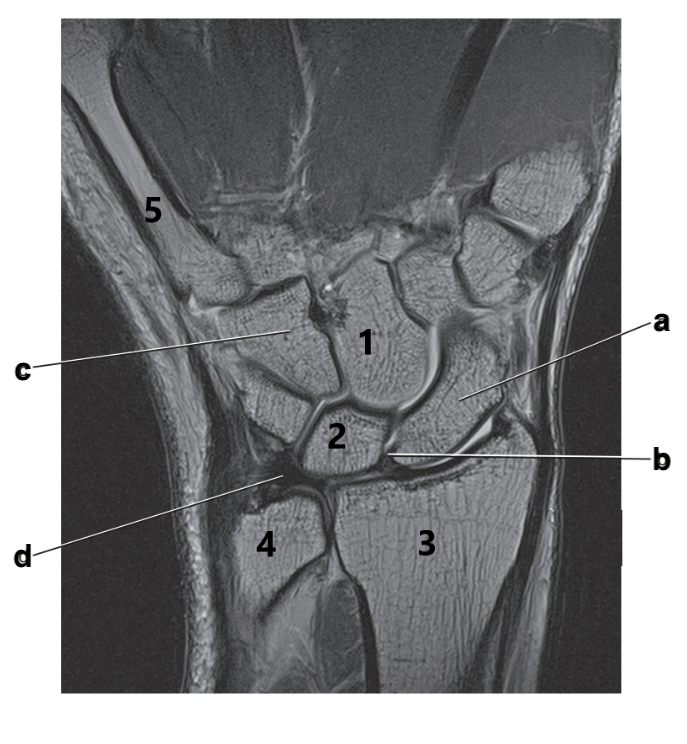

Hook of the hamate

What is # 4?

Ulna

Triangular fibrocartilage complex

Scaphoid

What ligamentous structure spans the wrist to create an enclosure for the passage of tendons?

Flexor retinaculum